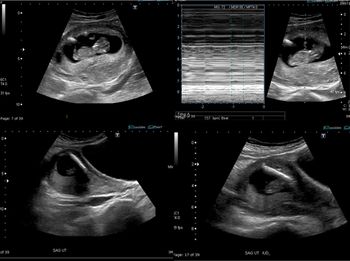

Ultrasounds can help identify pneumonia and its progression in children without exposure to ionizing radiation.